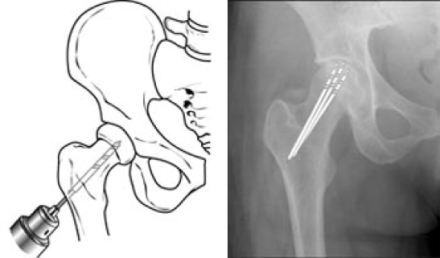

- Joint-Preserving Procedures

- Core Decompression

- Drills holes into femoral neck decrease pressure and allow for neovascularization

All SCFEs must be repaired surgically and the goals of surgery are to stabilize the diseased physis to prevent further slippage and avoid complications (AVN). Treatment of choice is a single cannulated screw placed in the center of the epiphysis.